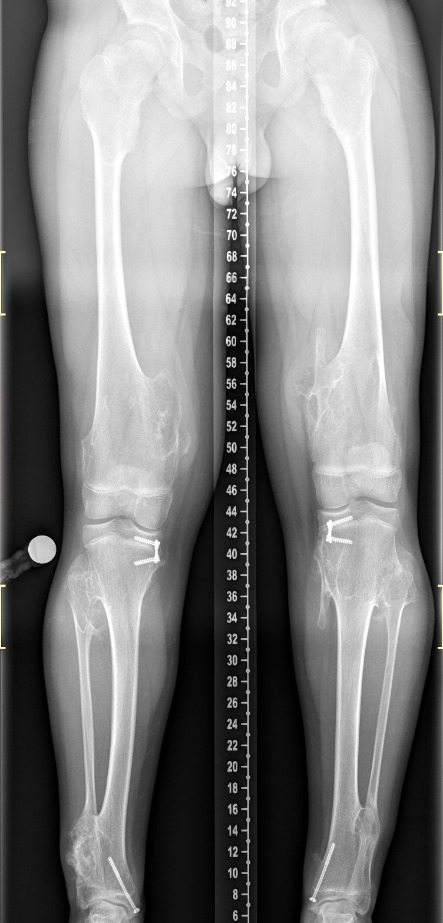

Πολλαπλά οστεοχονδρώματα

Οι εικόνες απεικονίζουν περιστατικό με πολλαπλά οστεοχονδρώματα, το οποίο χειρουργήθηκε από τον Δρ. Ζένιο.

Προ-εγχειρητικά

Μετ-εγχειρητικά